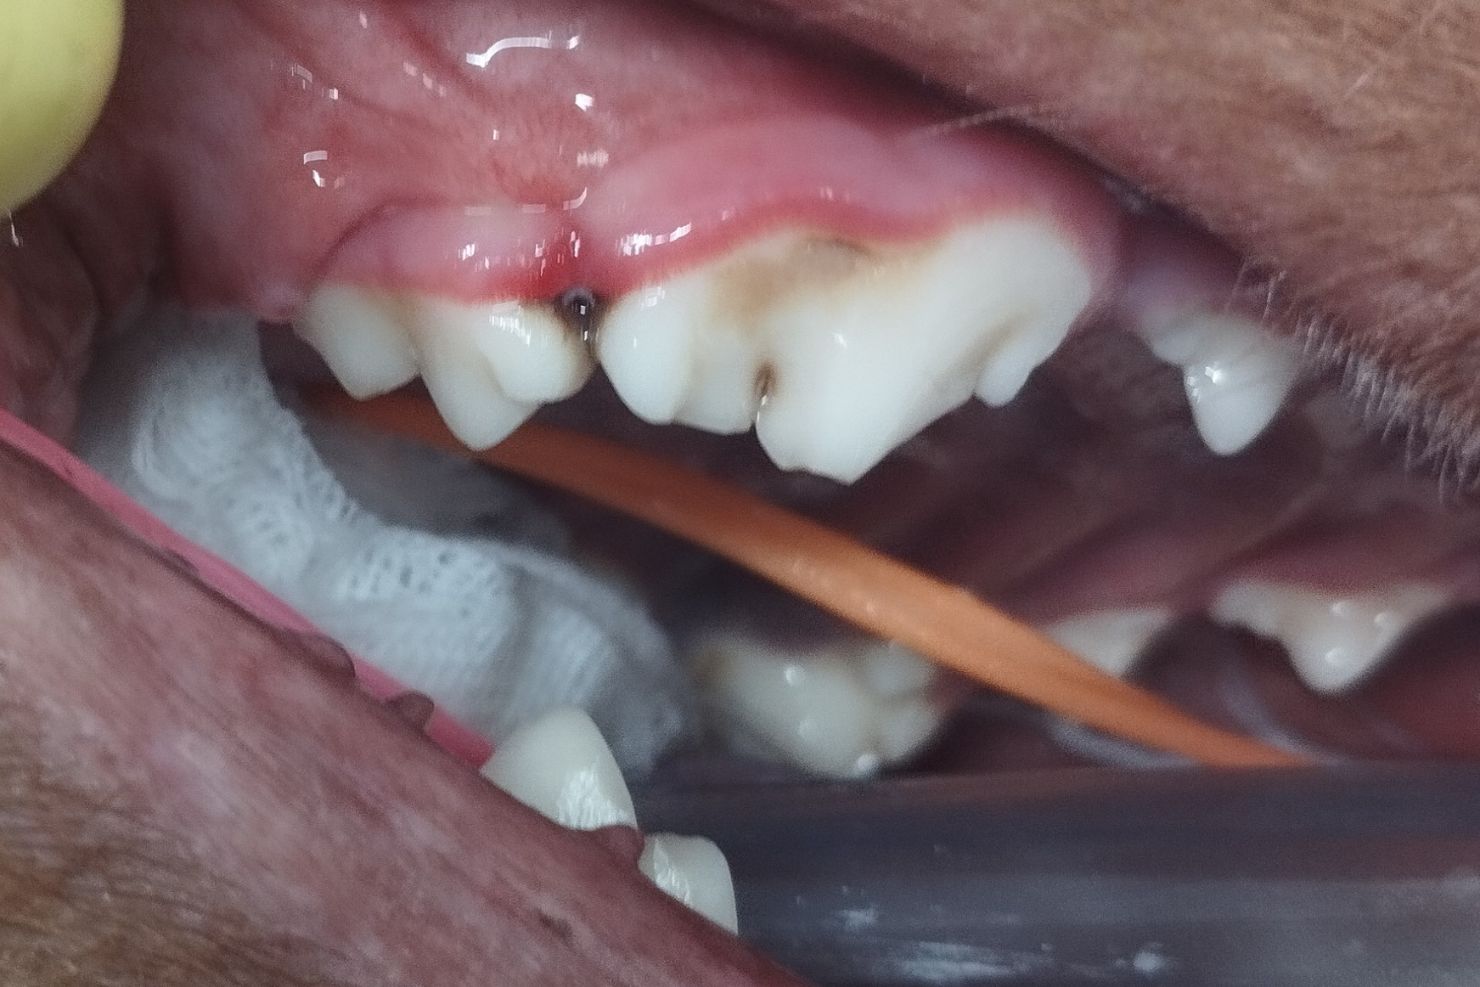

„Von der Zahnresorption sind bei der Katze am häufigsten der 307 und der 407 (also der zweite Prämolar im Unterkiefer, Anm.) betroffen“, berichtet Dr. Grünwald. „Wenn Sie dort eine Zahnfleischwucherung und / oder Rötung bemerken, ist die Wurzel bereits angegriffen; denn die Zahnresorption beginnt an der Wurzel und schreitet mit der Zeit bis zur Maulhöhle fort, wo es dann sehr schmerzhaft wird.“ Daher wird von tierärztlicher Seite oft erst spät eingegriffen. In den meisten Fällen ist die Resorption schon weit fortgeschritten und der Zahn muss extrahiert werden. Ist im Dentalröntgen nur eine geringe Veränderung an der Wurzel feststellbar und sind noch keine Anzeichen von Schmerz oder Entzündung ersichtlich, kann man einen konservativen Therapieversuch mit häufigem Monitoring (zumindest halbjährlich) erwägen. Die Extraktion der betroffenen Zähne ist bei Katzen oft schwierig, weil die Wurzeln zart und schmal und oft schon teilresorbiert und beschädigt sind. Es kann nur dann Schmerzfreiheit erreicht werden, wenn alle Wurzeln bis zur Wurzelspitze entfernt wurden. Deshalb ist auch ein Dentalröntgen nach der Extraktion unabdingbar!